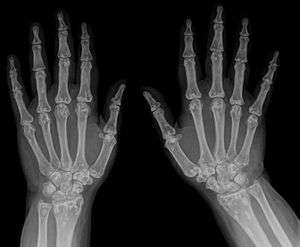

| Osteopoikilosis on an x-ray of the hands | |

The radiographic appearance of osteopoikilosis on an x-ray is characterized by a pattern of numerous white densities of similar size spread throughout all the bones. This is a systemic condition. It must be differentiated from blastic metastasis, which can also present radiographically as white densities interspersed throughout bone. Blastic metastasis tends to present with larger and more irregular densities in less of a uniform pattern. Another differentiating factor is age, with blastic metastasis mostly affecting older people, and osteopoikilosis being found in people 20 years of age and younger.